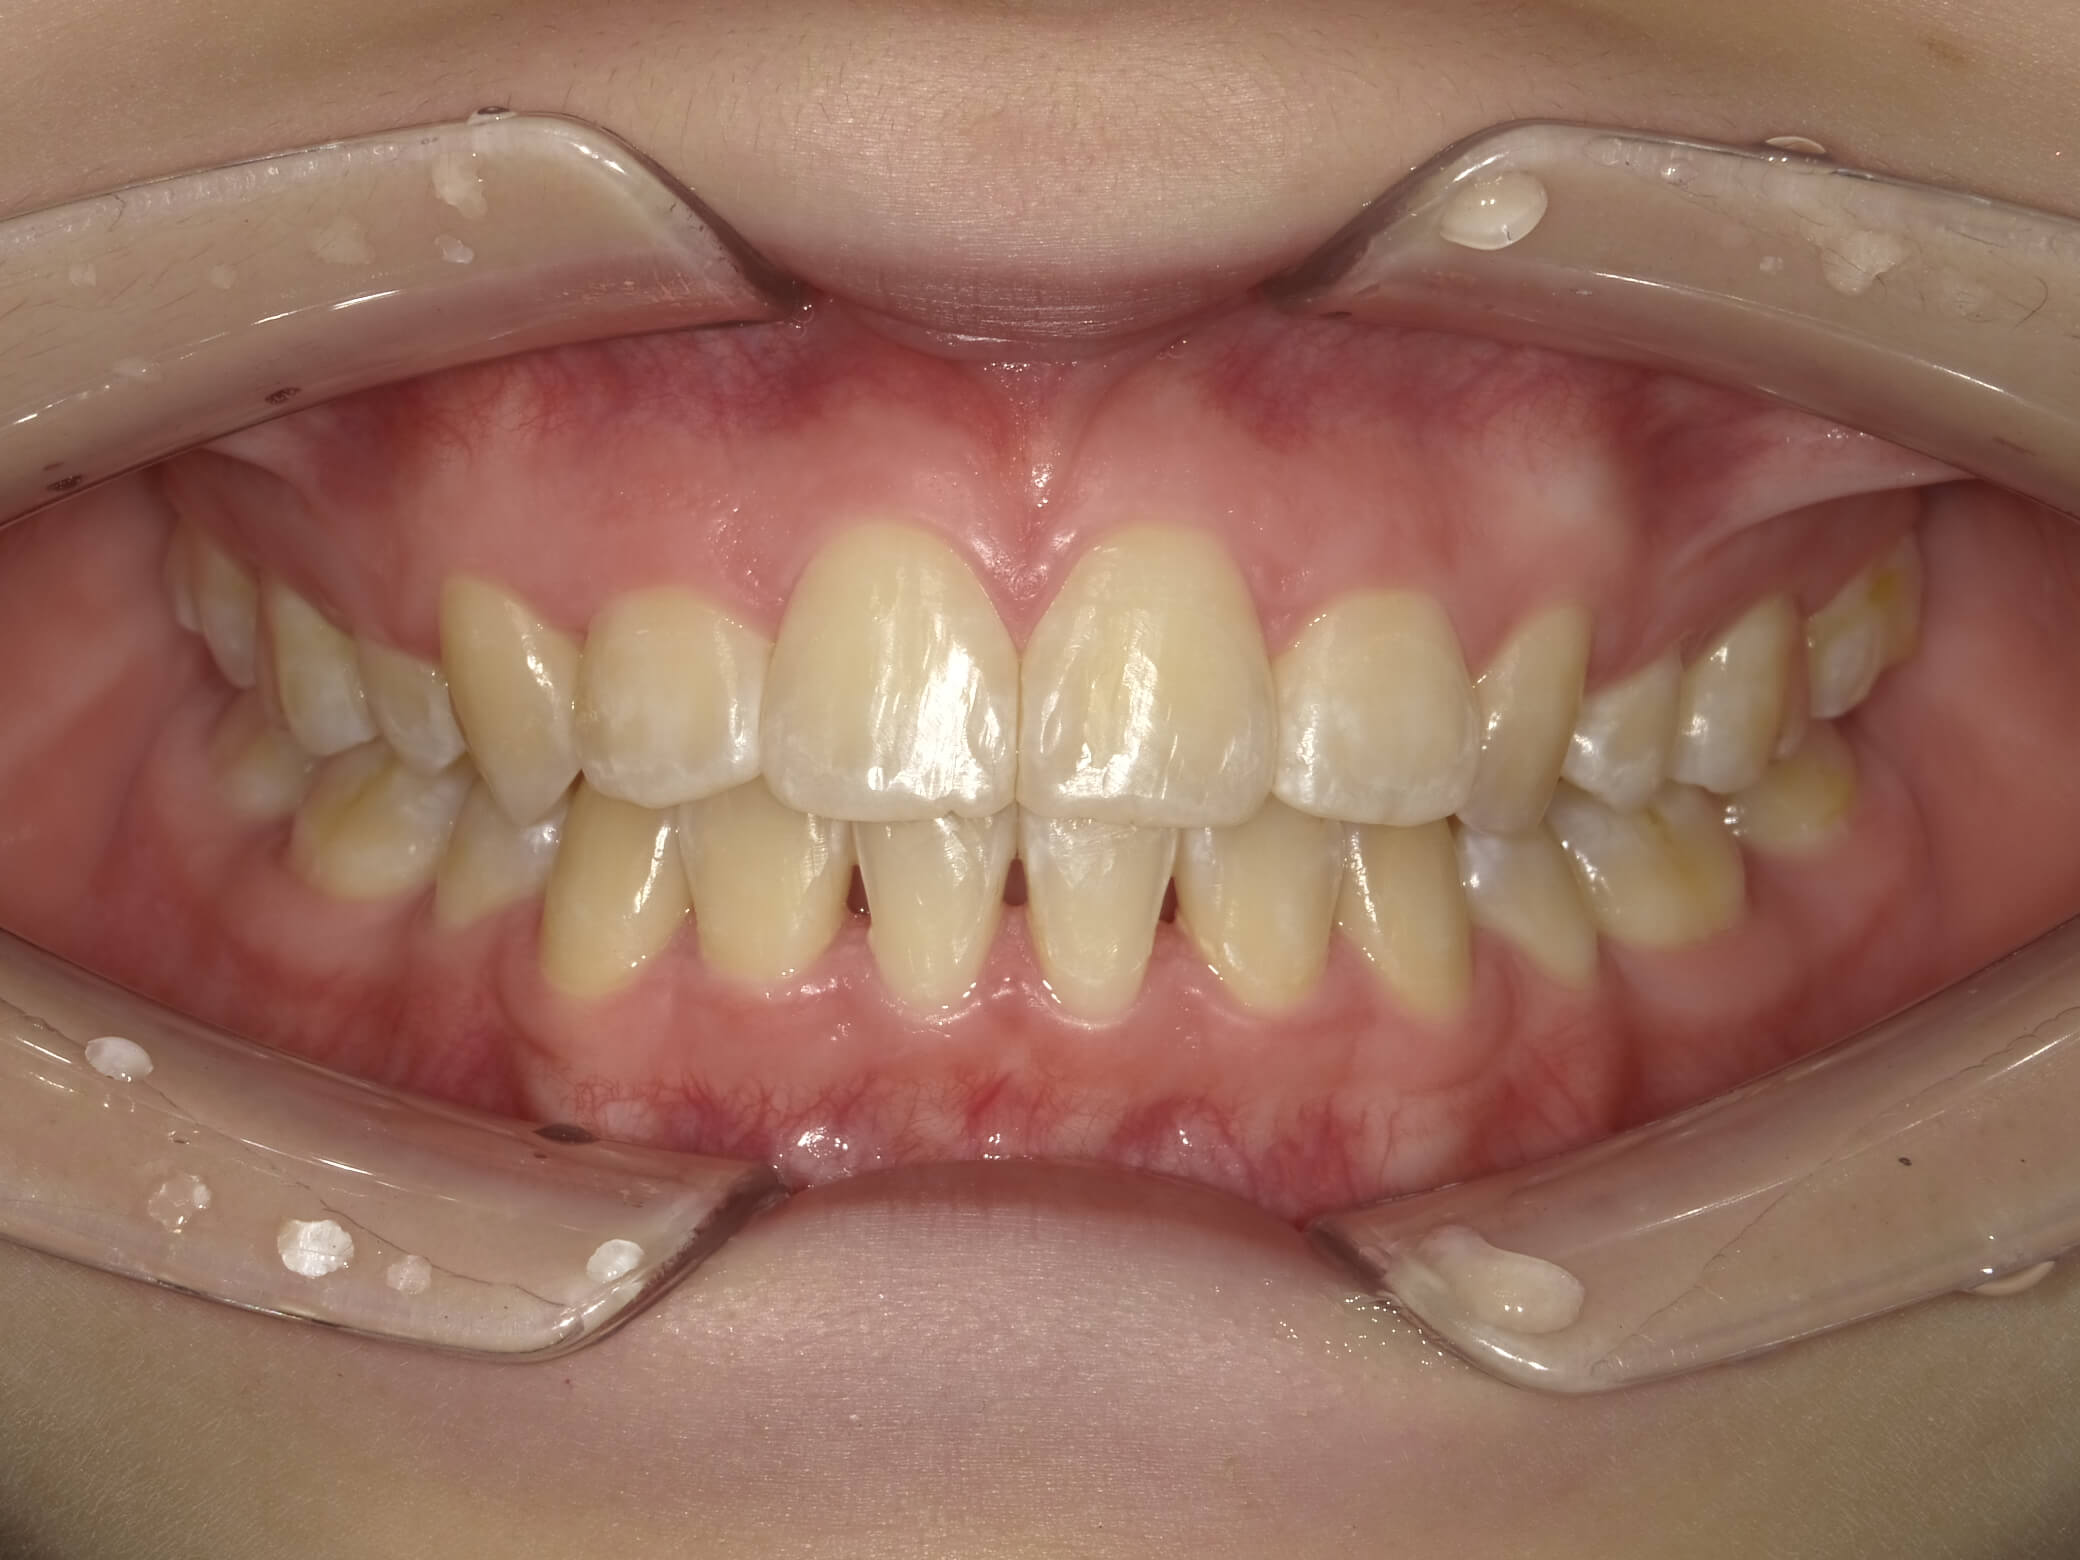

• 治療前